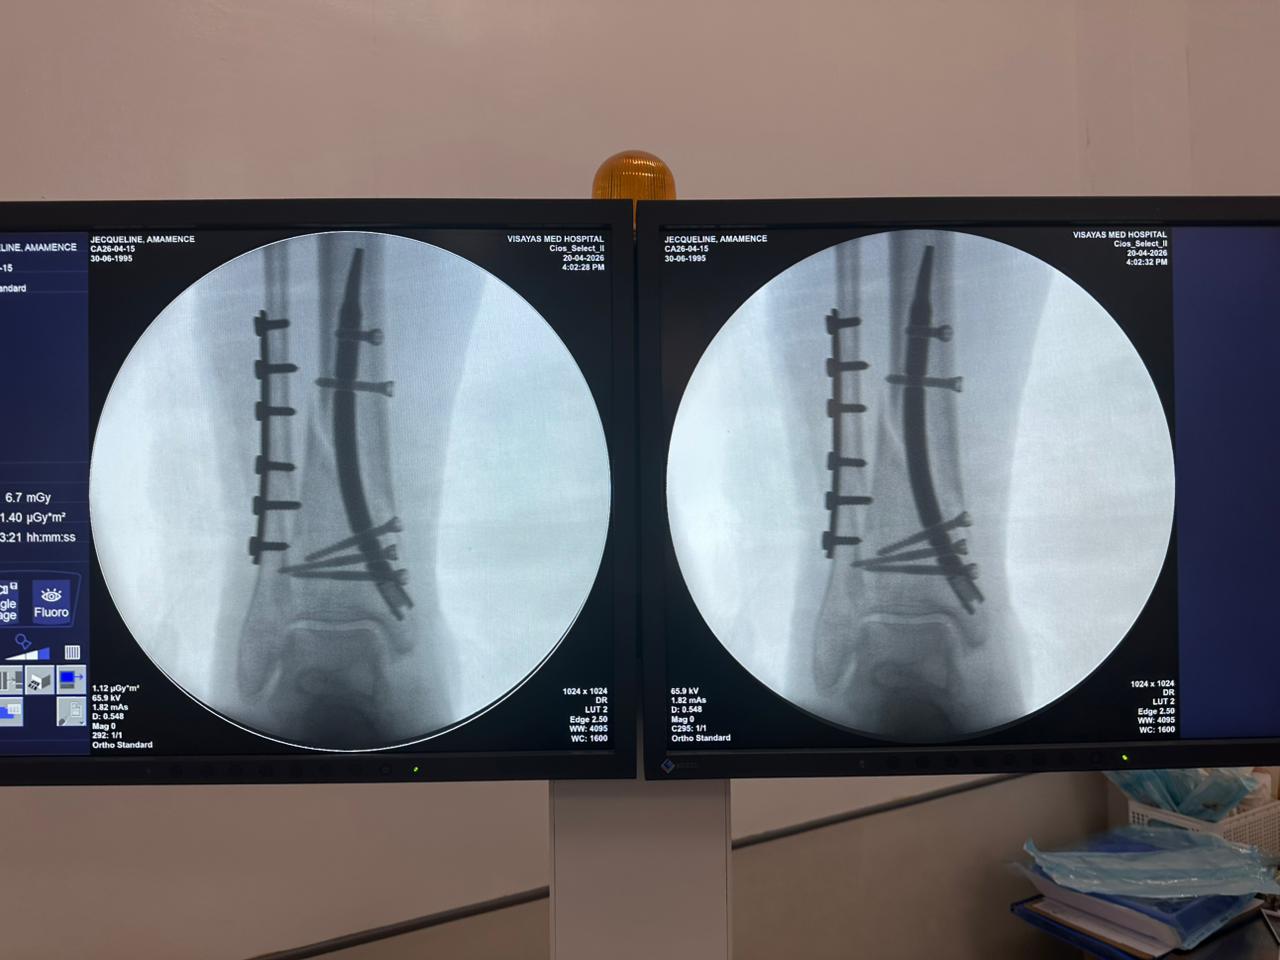

Caso di studio sulla fissazione del chiodo tibiale distale con supporto per placca peroneale

Paziente:

Paziente di 31 anni

Area Chirurgica:

Tibia e perone distali

Prodotto utilizzato:

Chiodo tibiale distale

Piastra di bloccaggio peroneale

Immagine:

Fluoroscopia intraoperatoria con arco a C, viste AP e laterali

Questo caso prevedeva la fissazione tibiale distale utilizzando un chiodo tibiale distale intramidollare. La fluoroscopia intraoperatoria ha confermato la posizione del chiodo, delle viti di bloccaggio distali e della fissazione della placca peroneale.